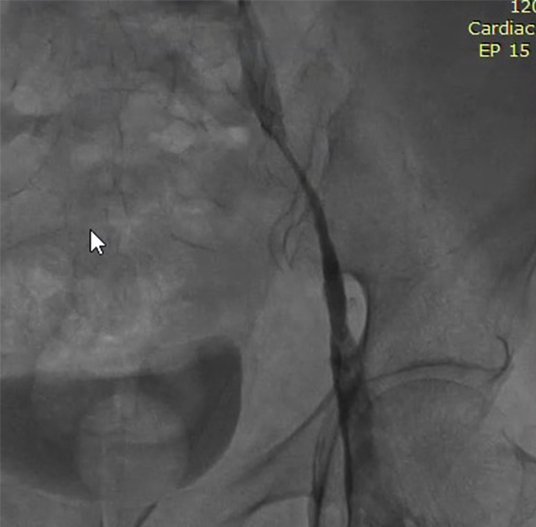

MRI/CT interpretation and Thrombectomy and stenting/ plasty for acute and recurrent stroke. Cerebral DSA

Thrombectomy – mechanical , pharmacological and combined therapy for acute stroke.

Outcomes observed in patients treated with image-guided, minimally invasive vascular procedures.

Results vary by patient and condition. Images are for educational purposes only.